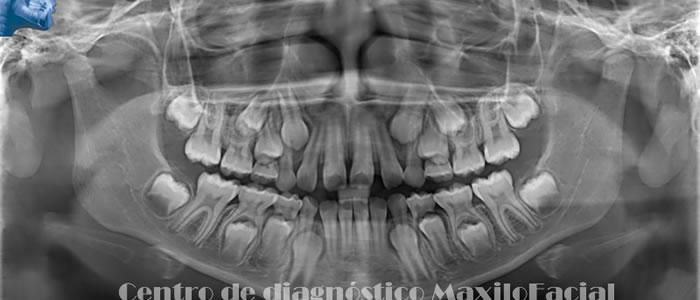

Radiografía Panorámica Dental

Permite obtener una apreciación global de los maxilares, a través de ella podemos detectar caries, enfermedad de las encías, quistes, tumores, fracturas, etc. Muchas de estas patologías son detectadas de forma casual, lo que la convierte en un estudio de protocolo a la hora de iniciar un tratamiento odontológico.

A continuación queremos mostrarle nuestra galería con algunas imágenes de casos llegados a Cedimax - Centro de Diagnóstico Maxilofacial, si requiriera más ejemplos de casos no dude en contactarse con nosotros.